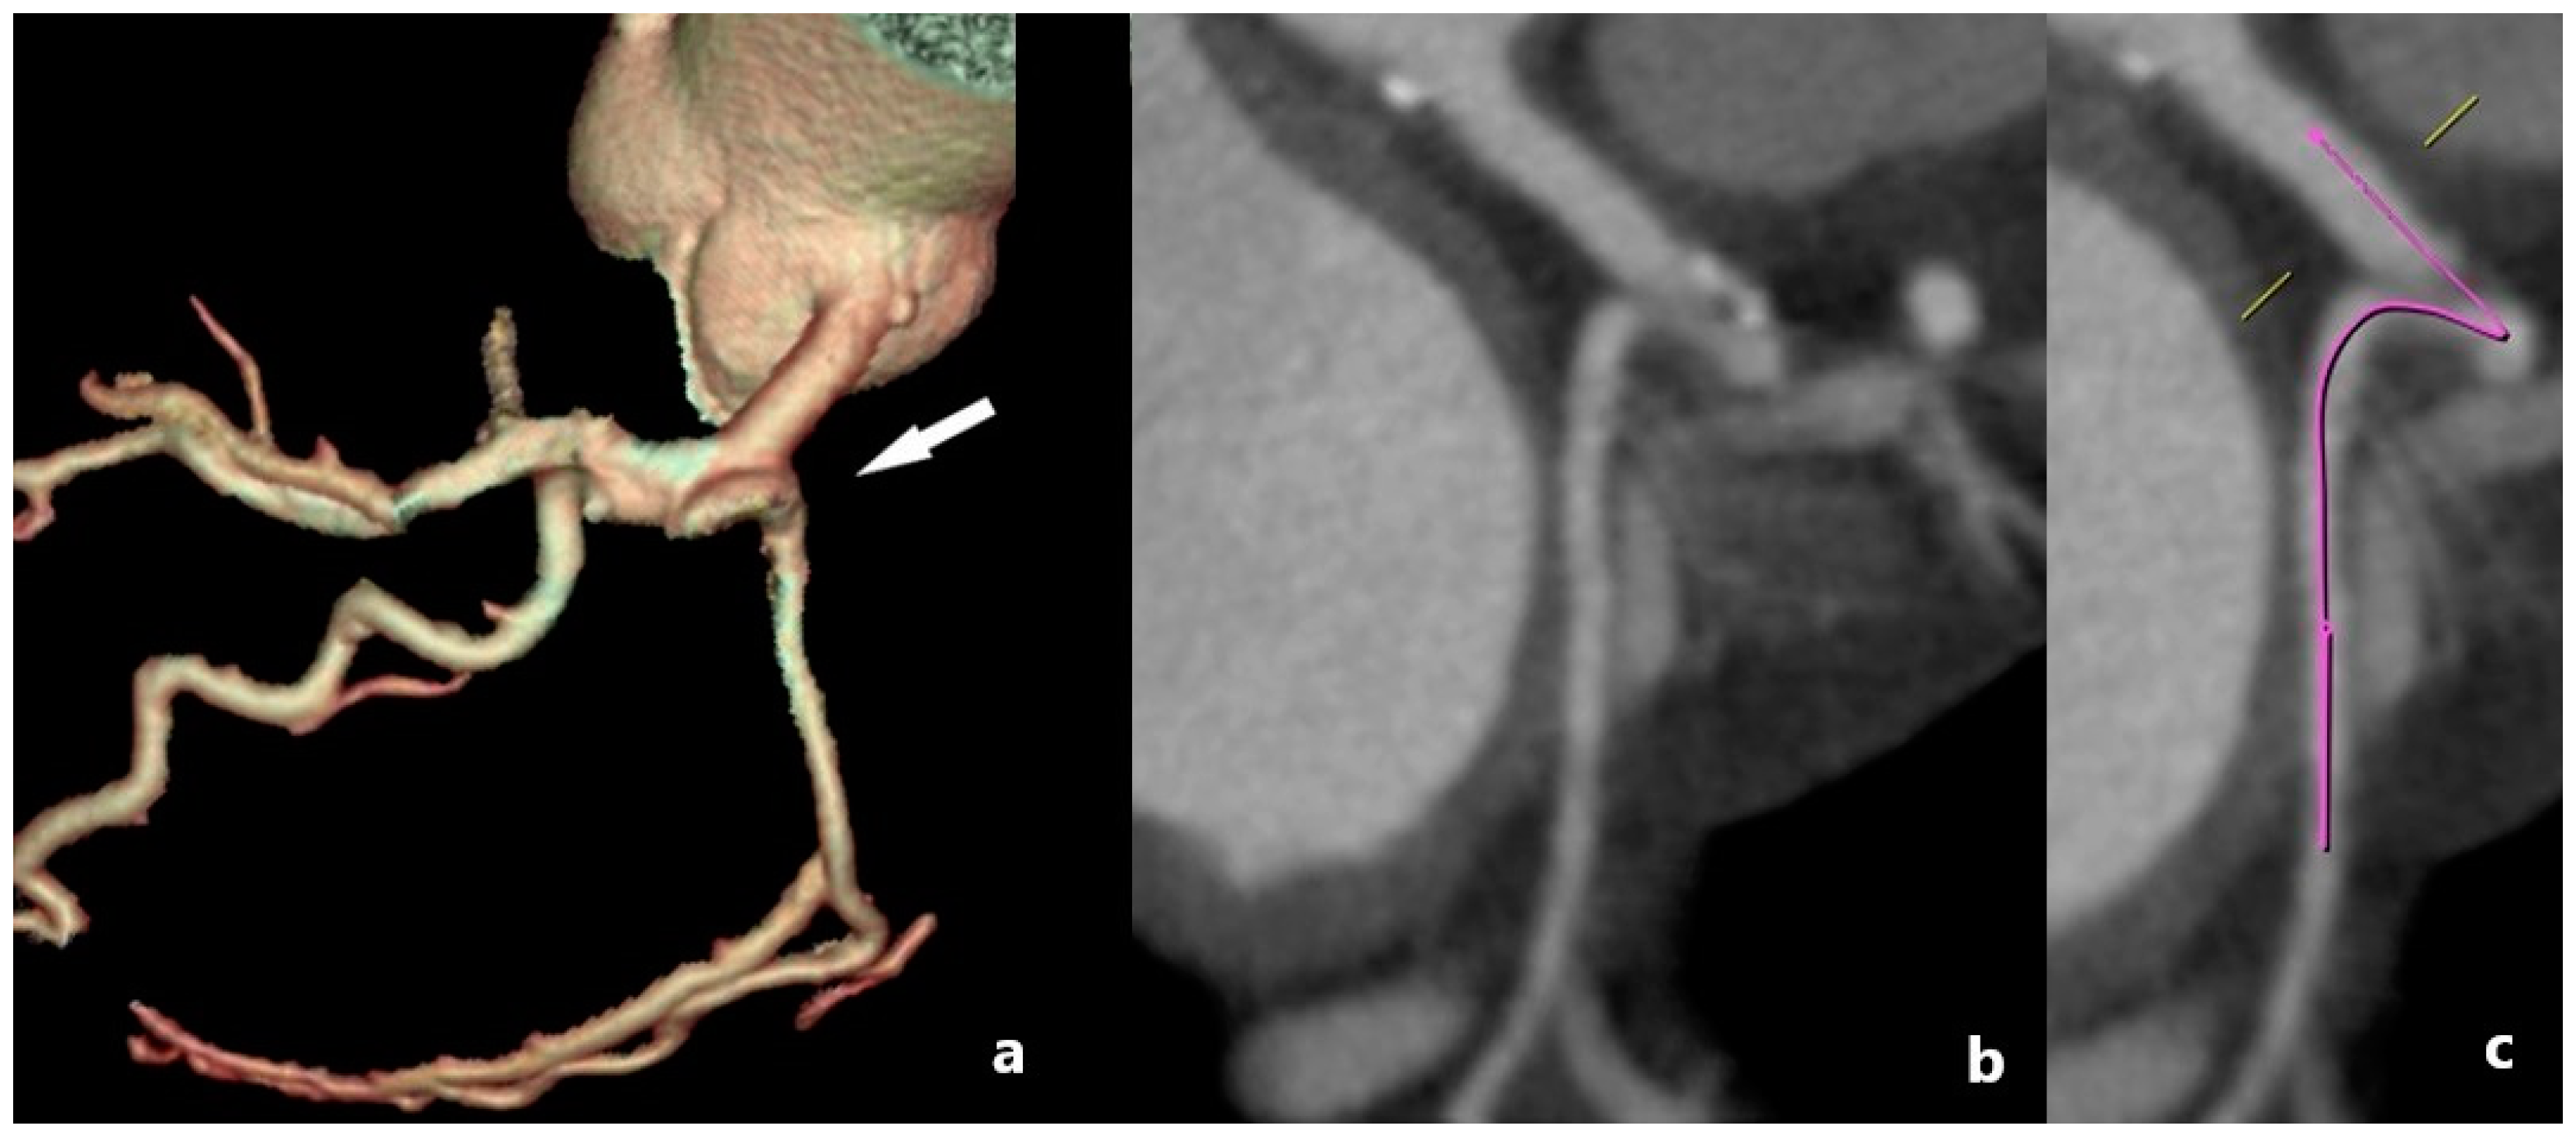

The anomalous origin of the coronary arteries is mostly an asymptomatic anomaly, with the exception of some rare cases when angina, syncope, heart failure, and sudden death may occur. The anomalous origin of LCX from the right coronary sinus is a prevalent congenital coronary variation (Figure 2a,b), with a documented prevalence of 0.18–0.67% in the literature [19]. It is typically a benign medical condition, but, in rare instances, individuals may experience atypical chest pain and discomfort [20].

White and Edwards first described an aberrant origin of the RCA in 1948 [21]. The anomalous origin of the RCA from the left sinus of Valsalva (Figure 2c,d) is a rare condition reported in 0.43% of patients undergoing MDCT coronary angiography [22], occurring more often in Hispanic individuals (0.25% of cases). This condition is usually asymptomatic but can be accompanied by anginal complaints, usually during exertion or rhythm disturbances [23].

Figure 2. Patients with aberrant origin of the coronary arteries. (a) Volume-rendered (VR) MDCT image of posterior view of the LCX arising from the right sinus of Valsalva (white arrow head), with its retrobulbar course (white arrow). (b) MDCT planar (axial) view of the LCX arising from the right sinus of Valsalva (red arrow head), with its retrobulbar course, moving between the aortic root and left atrium (red arrow). (c,d) MDCT image of posterior view of the single ostia and RCA arising from the left sinus of Valsalva (arrow in (c)), with retrobulbar position and further regular course (arrow head in (d)). With the noted retrobulbar course, these anomalies may occasionally lead to ischemia, especially if the vessel is compressed between great vessels, warranting further evaluation.